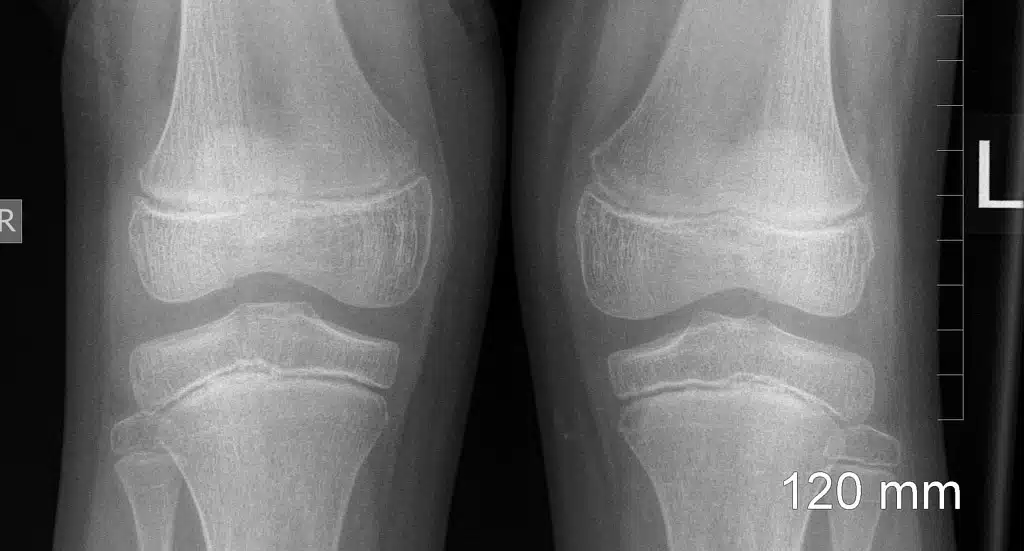

Anatomy or knee joint structure

The knee joints are one of the largest joints in the body. This joint is made up of three bones. Lower thigh, upper leg, and patella. The surface of the areas where these three bones are in contact is covered by cartilage, and the ease of movement of these three bones is due to the slippage of this surface. Inside the knee joint is a fluid that lubricates the cartilage and makes the joint easier to move. This fluid is known as articular fluid or synovial fluid. The knee miniscule is located between the leg bone and the femur. This C-shaped bone is like a cushion in the knee joint.

Osteoarthritis

Knee arthritis is the most important cause of knee joint in people over 40 years of age. Knee arthritis is the most common destructive disease in the joints of the body. In arthritis, the joints become dry and painful. Also, the patient may not use the joint because of the severe pain, so the muscles around the joint weaken and even – the joint movement becomes very difficult. In such a case the knee replacement surgery is necessary.